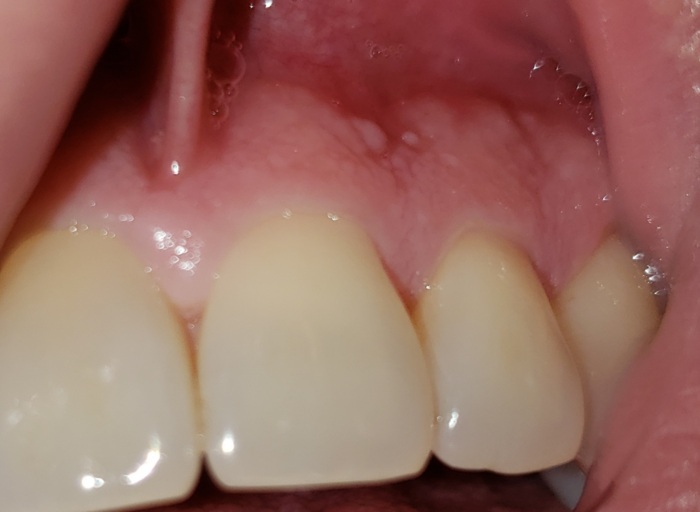

Hundreds of tiny clear blisters + petechiae on entire palate and uvula. Sore palate & throat. Cause?

Have been to a few doctors, but they don't know what this is. :( No pathogen found in recent swab tests/cultures. I thought it was herpetic stomatitis. Had 1 positive PCR test, but later tests were negative... and symptoms didn't resolve on Valacyclovir either. Biopsy was inconclusive too, but I believe they took a sample of the wrong spot. Symptoms wax and wane, but never leave. Been like this for 7 months in a row now. It started with a few clear blisters and irritation, then more and more blisters appeared. They coalesced and became firmer, thickening the skin on my hard palate. Skin below blisters is sore, with petechiae. The tiny clear blisters also have a red dot/small capillary(?) in them (see picture). My throat is often red and inflamed too. I'm desperate to get rid of it. My palate is sore almost the whole day, every day... and the blisters are irritating. :( Has anyone seen this before in their practice? Does anyone know what this could be?